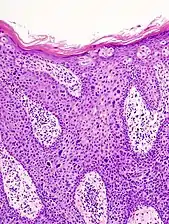

In situ disease

Bowen's disease is essentially equivalent to and used interchangeably with SCC in situ, when not having invaded through the basement membrane.[12] Depending on source, it is classified as precancerous[13] or SCC in situ (technically cancerous but non-invasive).[38][39] In SCC in situ (Bowen's disease), atypical squamous cells proliferate through the whole thickness of the epidermis.[12] The entire tumor is confined to the epidermis and does not invade into the dermis.[12] The cells are often highly atypical under the microscope, and may in fact look more unusual than the cells of some invasive squamous cell carcinomas.[12]

SCC in situ, high magnification, demonstrating an intact basement membrane.[12]